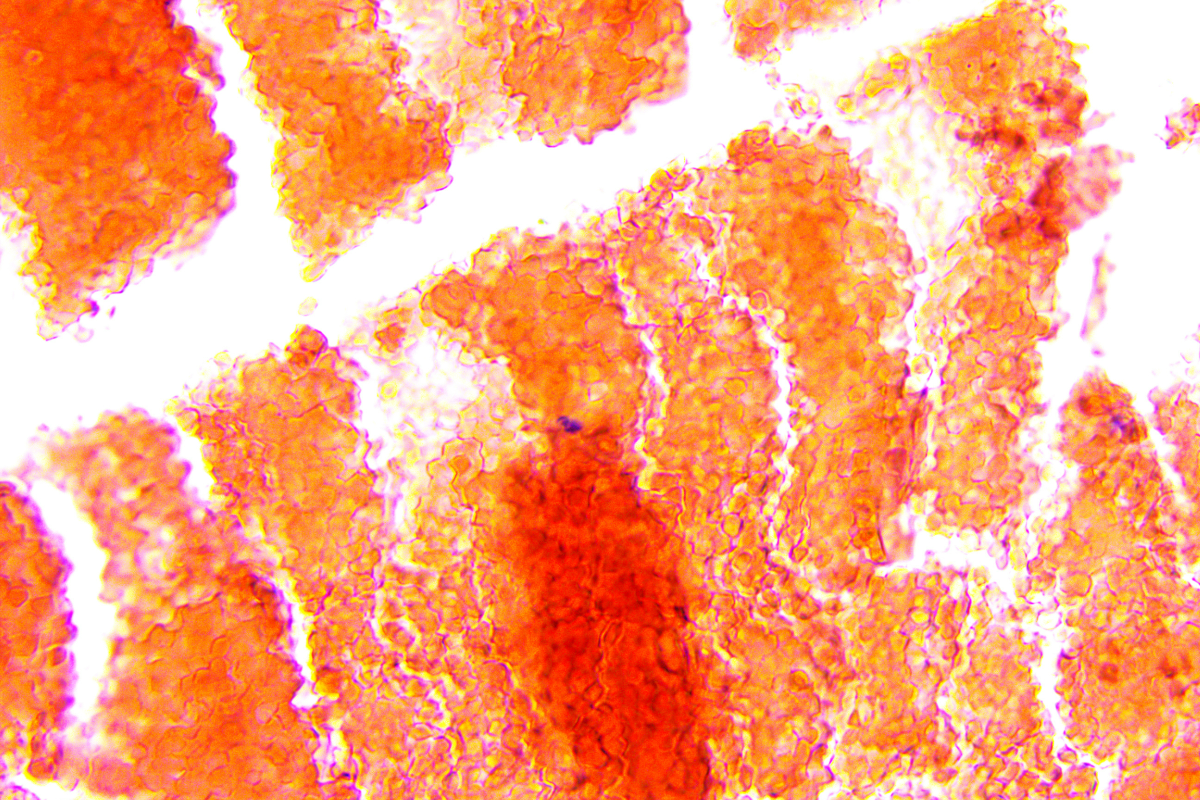

Stereotactic radiosurgery uses many precisely focused radiation beams to treat tumors and other problems in the brain, spine and other parts of the body. It is not surgery in the traditional sense because there's no incision; it uses 3D imaging to target high doses of radiation to the affected area with minimal impact on the surrounding healthy tissue. The procedure works by damaging the DNA of the targeted cells. The affected cells then lose the ability to reproduce, which causes tumors to shrink.